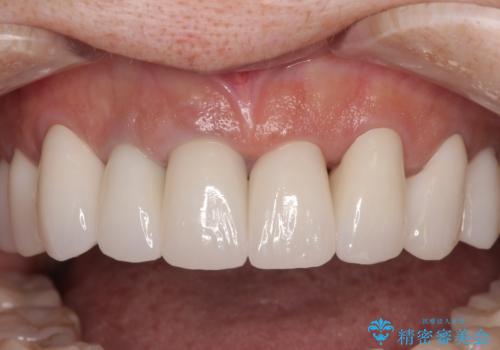

- セラミッククラウン

- 2009~2025年6月

- 000本